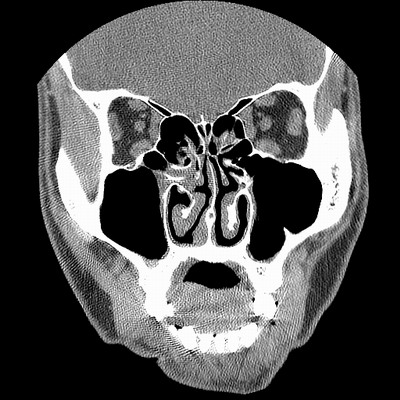

男,38岁,鼻塞、头痛2个月,要求鼻窦ct检查。

右侧上颌窦、蝶窦、筛窦、额窦及左侧上颌窦慢性炎症。

右侧鼻中隔左偏,右侧上颌窦、筛窦、额窦慢性炎性病变。右侧上颌窦开口粘膜增厚。

1)副鼻窦炎。2)右侧中鼻道及总鼻道粘膜息肉样变。3)双侧中下鼻甲肥大。4)鼻中隔轻度左突偏曲。